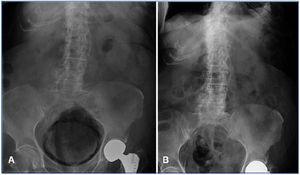

Presentamos el caso de una mujer de 86 años con antecedente de diabetes mellitus tipo 2 mal controlada, que ingresa por episodio de hipotensión arterial, fiebre, disuria y fracaso renal agudo en contexto de sepsis de etiología urinaria. Los datos de laboratorio mostraron: leucocitos 27.200 x 10e3/µl, glucosa 170 mg/dl, creatinina 5,1 mg/dl, urea 217 mg/dl, proteína C reactiva 232 mg/l. En la radiografía de abdomen se observa gas rodeando la silueta vesical, compatible con cistitis enfisematosa (figura 1 A).

En los cultivos no se observó crecimiento microbiológico. Se inició tratamiento con hidratación intravenosa, insulinoterapia y antibioterapia con meropenem, además de cateterización vesical, presentando adecuada respuesta. Se produjo recuperación sin complicaciones posterior a tres semanas de tratamiento antibiótico con normalización de función renal (figura 1 B).

Figura 1. Cistitis enfisematosa